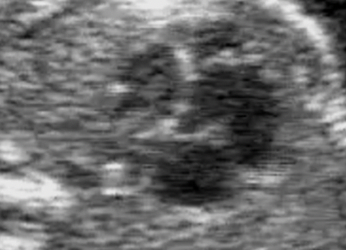

Per il mese di Dicembre SIEOG Giovani presenta il Webinar sullo screening delle cardiopatie congenite nel primo trimestre. La registrazione...